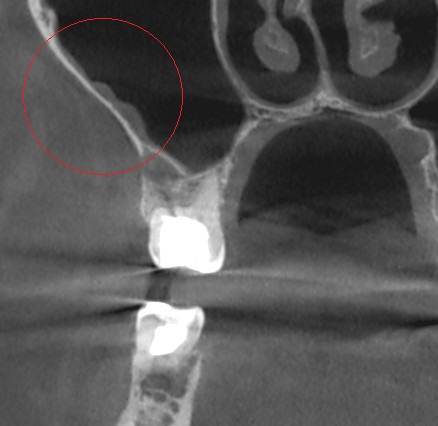

Александр В.В. Опубликовано 29 марта, 2023 Поделиться Опубликовано 29 марта, 2023 (изменено) Здравствуйте! Уже давно на шестом верхнем зубе есть гранулёма или киста размером 5-6 мм. Несколько лет назад пробовали класть кальций в каком-то виде, но, видимо, не помогло. Сейчас всё-таки решил перелечить этот канал, но эндодонтист сказал, что это только часть дела и надо делать все каналы. Кроме того, как я понял, проблема не в том канале, который запломбирован, а в том, который проходит рядом с ним и не был обнаружен и запломбирован. На этом снимке это верхний левый корень и в его правой части темное пятно - это вроде и есть тот ненайденный канал. Здесь видна гранулёма и запломбированный канал (корень слева). А здесь справа от запломбированного канала (левого корня), тот самый незапломбированный. Но у меня есть сомнения по поводу такого вывода, потому что в других каналах можно обнаружить более очевидные "темные каналы" в зависимости от среза. На этих снимках обращаю ваше внимание на правый канал. Если нужно, могу предоставить другие проекции, потому что имею диск с данными КЛКТ. Вопросы. 1. Действительно ли на снимке ненайденный канал на корне зуба с гранулёмой? 2. Возможно ли перелечивание одного канала с гранулёмой или кистой или нужно распломбировать сразу все каналы во всех корнях? 3. Если на снимке всё-таки ненайденный канал, то не кажется ли вам, что он прямой, а не изогнутый? Если прямой, его может обработать терапевт без использования микроскопа? Изменено 29 марта, 2023 пользователем Александр В.В. Ссылка на комментарий

Александр В.В. Опубликовано 16 декабря, 2023 Автор Поделиться Опубликовано 16 декабря, 2023 Здравствуйте! Провёл лечение этого зуба, а гранулёма и боли остались. Прошу совета. Рассказываю по порядку. 1. До перелечивания этого зуба (шестнадцатый) были постоянные воспаления десны из-за разрушенной коронки зуба и неровных краёв пломбы в поддесневой части со стороны отсутствующего соседнего зуба. Также были боли при прикосновении пальцем десны в проекции корней зуба со стороны щеки, то есть, примерно там, где находится гранулёма. При этом припухлости этой области я не замечал. 2. На первом этапе лечения были рассверлены каналы, в том числе и ранее не найденный, и на 7 дней заложен препарат для растворения остатков пломбировочного материала. Также была установлена временная пломба. Уже после первого посещения я заметил, что ушла боль при прикосновении пальцем проекции корней. Но 2-3 дня периодически происходило выделение бурой жидкости из носа в виде капель при наклоне головы. Зуб не болел, ничего не опухало. 3. На втором этапе были удалены остатки пломбировочного материала из корней, заложен препарат кальция для «лечения» и снова установлена временная пломба. Точно не знаю, для чего применяется кальций. То ли как антисептическое средство, то ли для восстановления костной ткани. Опять несколько дней наблюдалось выделение жидкости из носа. Болей не было три недели ни в области проекции корней, ни десны со стороны отсутствующего зуба, а потом опять начала болеть десна скорее всего из-за разрушения временной пломбы. С кальцием ходил 30 дней. 4. На третьем этапе были запломбированы все каналы, установлен стекловолоконный штифт и восстановлена коронка зуба с помощью пломбировочного материала, но при этом зуб был выведен из прикуса. Стоматолог предупредил, что зуб может болеть 2 недели, как это бывает после пломбирования. На этот раз никаких выделений из носа не было. Болей или опухания тоже не было. Но примерно через 8 дней опять начала болеть десна, как со стороны отсутствующего зуба, так и в проекции корней, причём, мне кажется, что даже сильнее, чем раньше. Возможно, это связано с тем, что я начал пытаться жевать этим зубом и более смело пользоваться зубной щёткой. Новые снимки зуба показали, что гранулёма осталась на своём месте. Вопросы. 1. Нормально ли то, что гранулёма осталась, несмотря на проведённое лечение? 2. На снимке потемнение десны справа от зуба – это воспаление? В чём может быть его причина? 3. Что появилось в пазухах? На снимках, сделанных год назад, этого не было. 4. Почему проходили боли на первых этапах лечения и появились снова после его окончания? 5. Что делать дальше? Ждать, что само пройдёт или принимать какие-то меры? Систематически таблетки не пил. Только однократный приём НПВС после каждого посещения стоматолога. Сейчас провожу полоскание зуба различными препаратами и мажу разными мазями и гелями для дёсен. Ссылка на комментарий